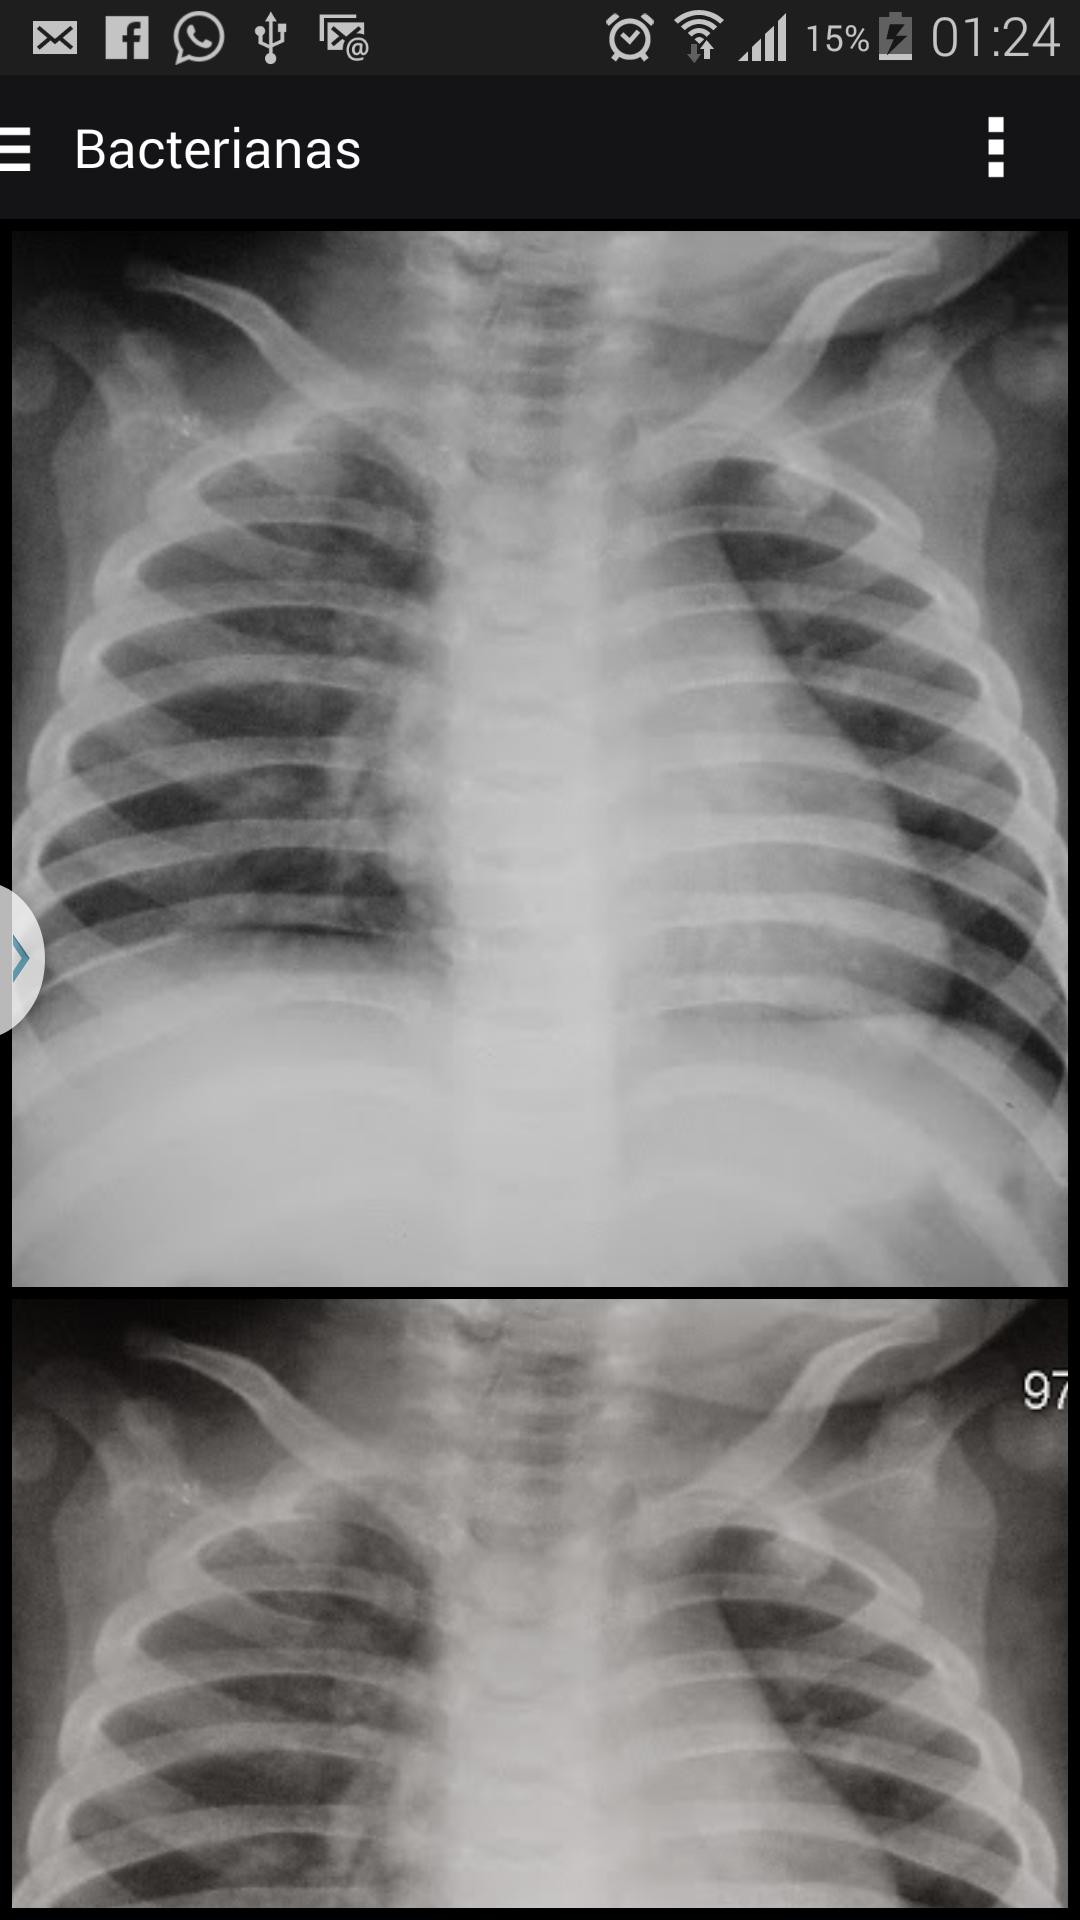

Images aux rayons X pour soutenir le diagnostic de la pneumonie chez les enfants

La rayon de poitrine X est considérée par l'Organisation mondiale de la santé (OMS) comme la meilleure méthode actuellement disponible pour le diagnostic de la pneumonie dans la pratique clinique quotidienne. Les études sur les variations interobservantes sont courantes dans tous les domaines de la médecine, cependant, prédominent dans les études d'image, étant donné que dans ce domaine, la performance de l'observateur représente la partie fragile, contrastant avec l'avancement technologique, obtenu au cours de la dernière décennie.

Les interprétations qui diffèrent d'un "consensus" par un comité d'observateur expérimenté peuvent être appelées "erreur". La variation entre les observateurs se produit lorsqu'il y a une erreur par un observateur, mais comprend également des cas où il y a une différence d'opinion générale sur ce qu'une interprétation correcte représente. Des erreurs et des variations ont été étudiées notamment dans l'interprétation des radiographies.

Facteur fondamental de l'or »dans l'évaluation des tests de diagnostic. Dans le cas du diagnostic radiographique de la poitrine, en particulier dans l'enfance, la précision de l'interprétation de l'image est subjectivement évaluée par un accord inter et intraobserving, car il existe rarement un modèle qui peut être utilisé comme référence (standard) dans le diagnostic de pneumonie.